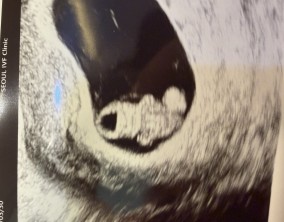

반복된 유산 끝, PGT로 찾아온 기적